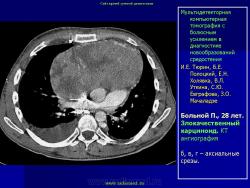

Средостение.  "Опухолевый рост".